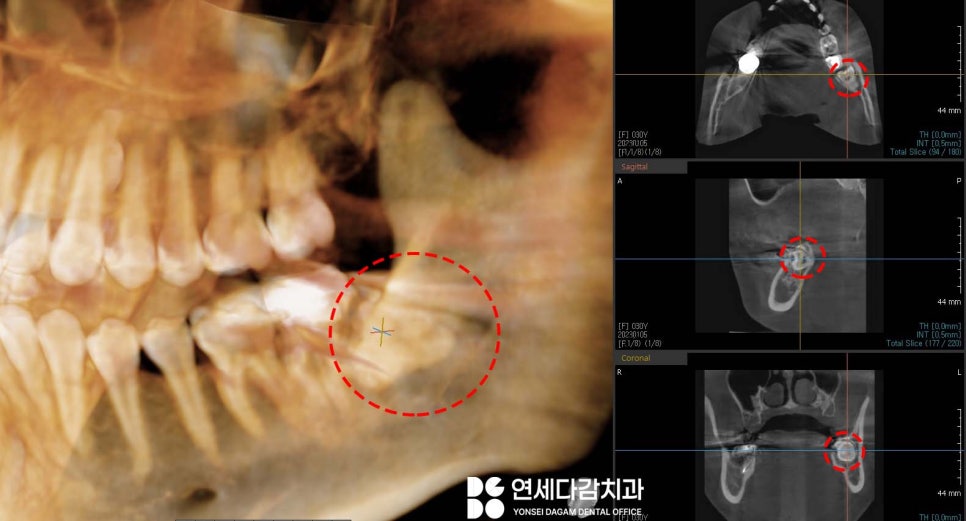

또한 부분 맹출 된 사랑니 부위에

음식물이 많이 끼면서

잇몸이 심하게 붓기도 합니다.

붓기가 심하면 입이 잘 다물어지지

않는 경우도 있으니

이런 경우엔 사랑니도 같이 치료하는 것이 좋습니다.

턱관절 치료와 함께

평소 불편했던 사랑니도 발치하여

삶의 질을 개선할 수 있었습니다.